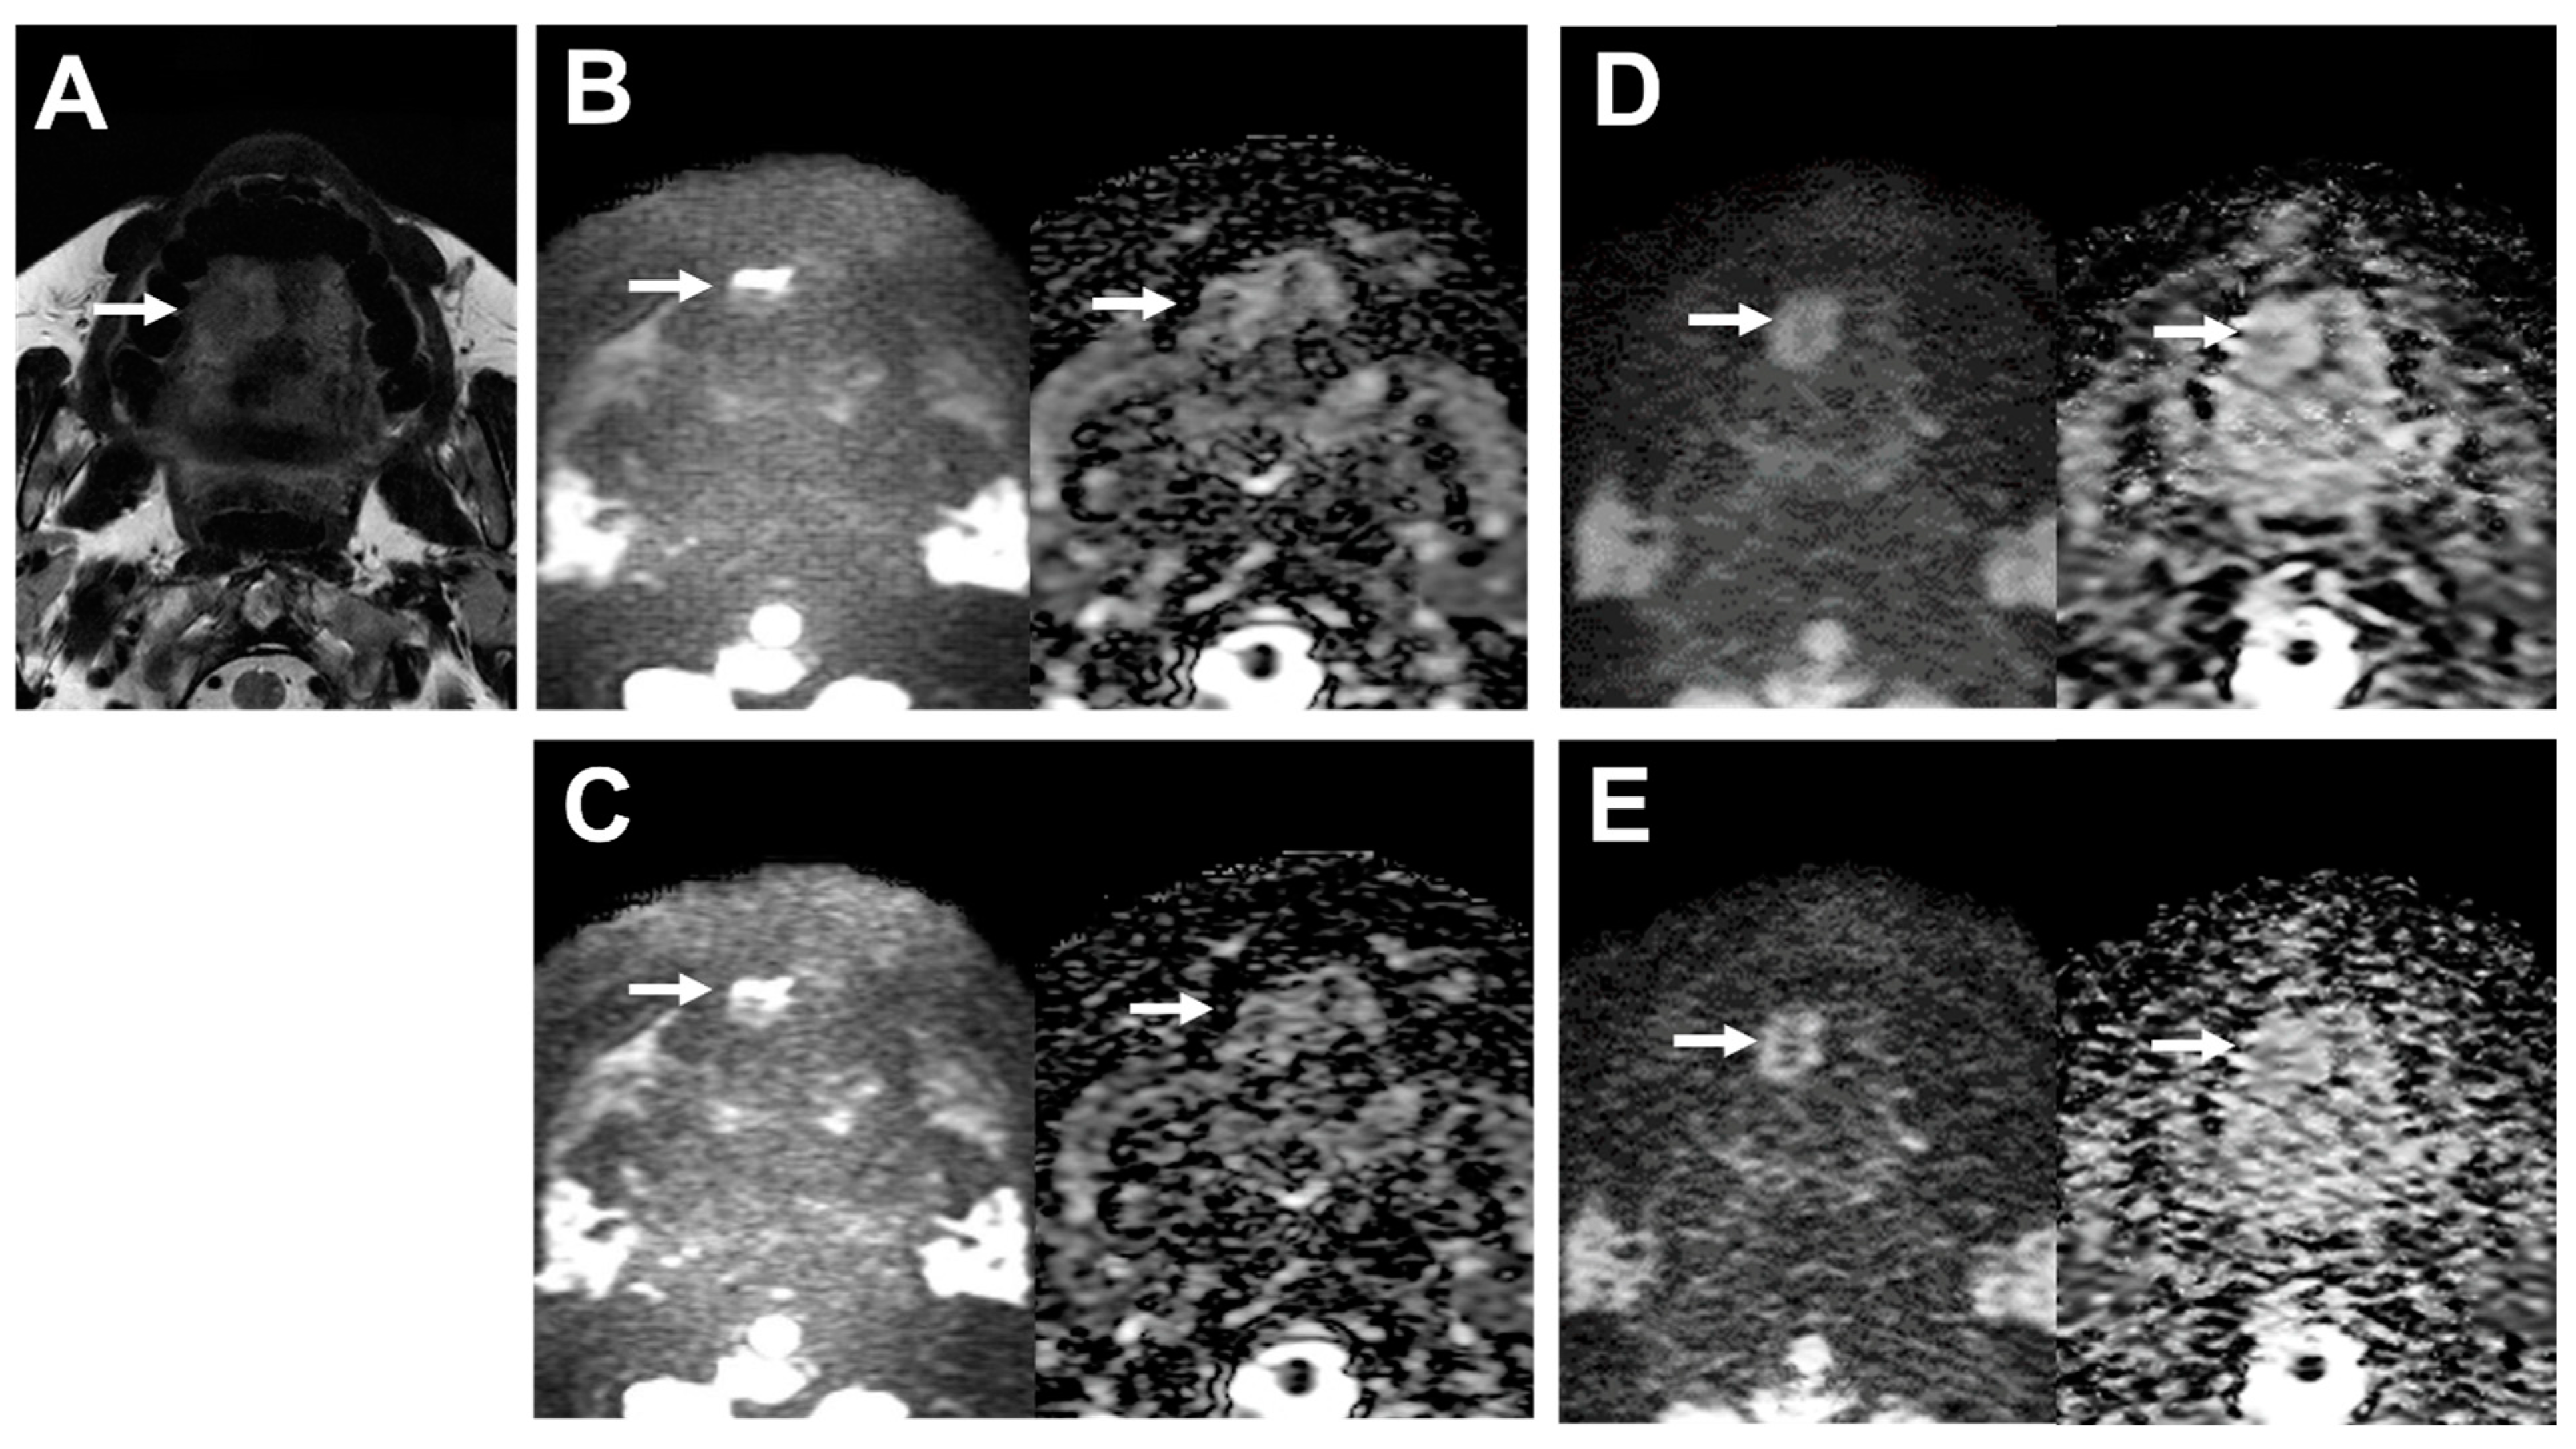

A representative case is shown in Figure 3.

Figure 3. 39-year-old male patient with oral cavity squamous cell carcinoma. (A) T2WI clearly depicts the lobulated shape of oral cavity cancer at the right side of the tongue (arrow). (B) (L to R, original DWI image and ADC map) Image of the tumor on DWI obtained by EPI with DLR shows deformation (arrows). SNR of the tumor was 4.43, and the deformation ratio (DR) compared with T2WI was 0.60. (C) (L to R, original DWI image and ADC map) The image of the tumor on DWI obtained by EPI without DLR is also deformed (arrows). SNR of the tumor was 4.58, and the deformation ratio (DR) compared with T2WI was 0.60. (D) (L to R, original DWI image and ADC map) The image of the tumor on DWI obtained by FASE with DLR is less deformed (arrows). SNR of the tumor was 7.08, and the deformation ratio (DR) compared with T2WI was 0.01. (E) (L to R, original DWI image and ADC map) The image of the tumor on DWI obtained by FASE without DLR is deformed (arrows). SNR of the tumor was 4.47, and the deformation ratio (DR) compared with T2WI was 0.21.